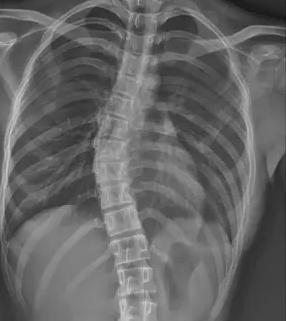

當(dāng)前青少年脊柱側(cè)彎診療體系面臨系統(tǒng)性困境。在篩查環(huán)節(jié),傳統(tǒng) X 線測量 Cobb 角雖為金標(biāo)準(zhǔn),但輻射風(fēng)險限制其大規(guī)模應(yīng)用;現(xiàn)有初篩手段假陽性率高達(dá) 35%,而低輻射智能篩查技術(shù)在基層醫(yī)院普及率不足 12%,導(dǎo)致大量病例漏診。疾病管理鏈條存在顯著斷層,Cobb 角<10° 的輕癥患者因缺乏標(biāo)準(zhǔn)化干預(yù)方案,錯失黃金矯正期。保守治療領(lǐng)域,支具治療依從性不足 40%,定制精度誤差超 15%,全國注冊矯形師缺口達(dá) 83%;物理治療資源配置失衡,70% 的基層醫(yī)療機構(gòu)尚未建立規(guī)范康復(fù)訓(xùn)練體系。

針對上述痛點,醫(yī)療科技企業(yè)與科研機構(gòu)正聯(lián)合構(gòu)建智慧防治體系。迪納醫(yī)療研發(fā)的全幅 Dira-DUC 技術(shù),通過 AI 輔助三維重建實現(xiàn)單次 0.02mSv 低劑量成像,較傳統(tǒng)設(shè)備輻射量降低 87%。其自主研發(fā)的脊柱側(cè)彎風(fēng)險預(yù)測模型,整合 120 萬例臨床數(shù)據(jù),可精準(zhǔn)識別高危人群,篩查準(zhǔn)確率提升至 92%。診療環(huán)節(jié)引入智能 Cobb 角測量算法,將人工測量誤差從 ±5° 壓縮至 ±1.2°。在支具治療方面,智能監(jiān)測支具內(nèi)置壓力傳感器與物聯(lián)網(wǎng)模塊,實時反饋佩戴數(shù)據(jù)并生成個性化調(diào)整方案。物理治療領(lǐng)域,標(biāo)準(zhǔn)化訓(xùn)練課程已納入國家衛(wèi)健委基層康復(fù)指南,配備 AI 動作捕捉系統(tǒng)的智能訓(xùn)練艙正在全國 127 家縣級醫(yī)院推廣。